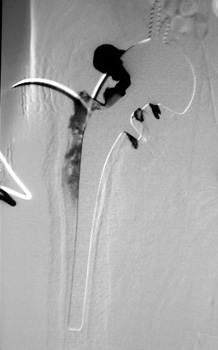

Arthrographic evidence of looseningcontrast enters

abnormally widened interface Gruen zone 1 and 2